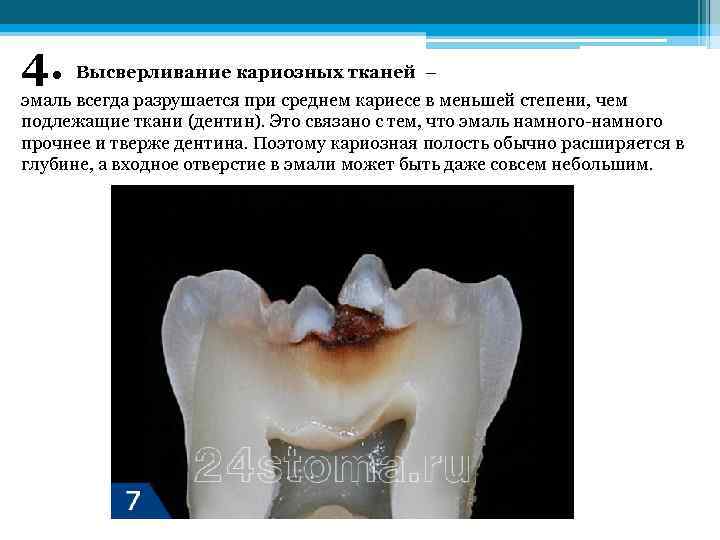

4. Высверливание кариозных тканей – эмаль всегда разрушается при среднем кариесе в меньшей степени, чем подлежащие ткани (дентин). Это связано с тем, что эмаль намного-намного прочнее и тверже дентина. Поэтому кариозная полость обычно расширяется в глубине, а входное отверстие в эмали может быть даже совсем небольшим.

4. Высверливание кариозных тканей – эмаль всегда разрушается при среднем кариесе в меньшей степени, чем подлежащие ткани (дентин). Это связано с тем, что эмаль намного-намного прочнее и тверже дентина. Поэтому кариозная полость обычно расширяется в глубине, а входное отверстие в эмали может быть даже совсем небольшим.